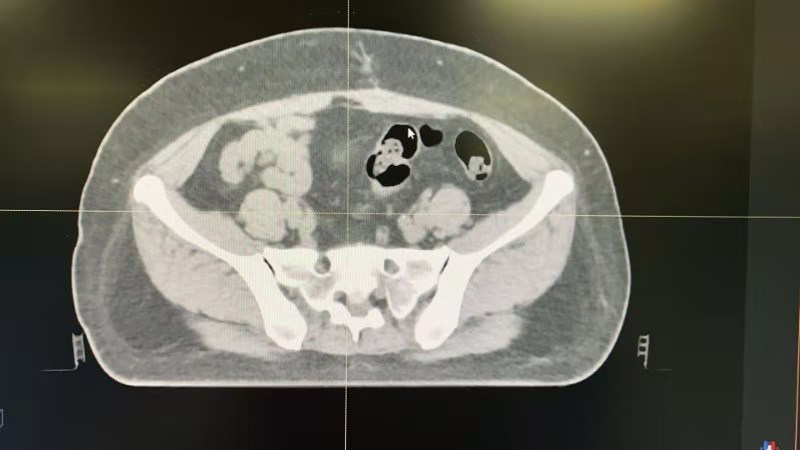

图3 俯卧体位CT图像

目前已经投入临床使用,在获得的临床数据中,其治疗时候体位误差控制在了5mm以内,明显降低了射线对患者的肠道,膀胱的副作用。